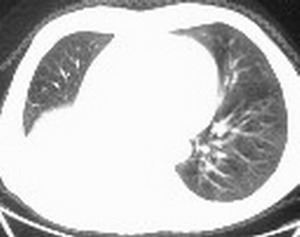

标题: CT6943:[讨论]胸部,M/67Y,体检发现。

ct值约12hu。

ct值约12hu

右肺下叶支气管闭塞,中间段支气管狭窄,下叶不张,胸腔及叶间积液.中心型肺癌伴下叶肺不张.胸腔和叶间积液.

右肺下叶支气管闭塞,伴下叶实变不张。建议增强及纤支镜。

右肺下野后部均匀低密度影,边缘锐利,前缘外突(不支持肺不张),纵隔内未见明显肿大淋巴结,右下肺门结构显示欠清,临床资料太过简单,考虑右侧后胸部包裹性积液。其他待排。建议密切结合临床其他检查。